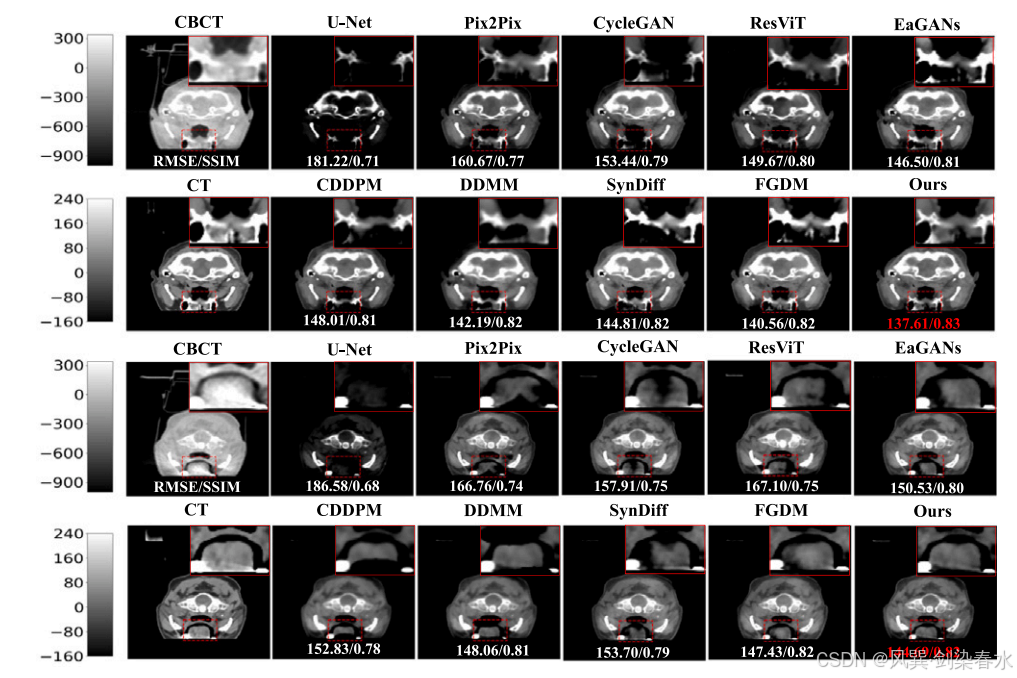

Figure 5 | 头部测试数据集可视化:第二行和第四行显示了红色虚线框标记的放大区域,定量结果位于预测图像底部,CBCT 的显示窗口范围为 [−1000,340] HU,而 CT 和 sCT 的显示窗口则为 [−160,240] HU;